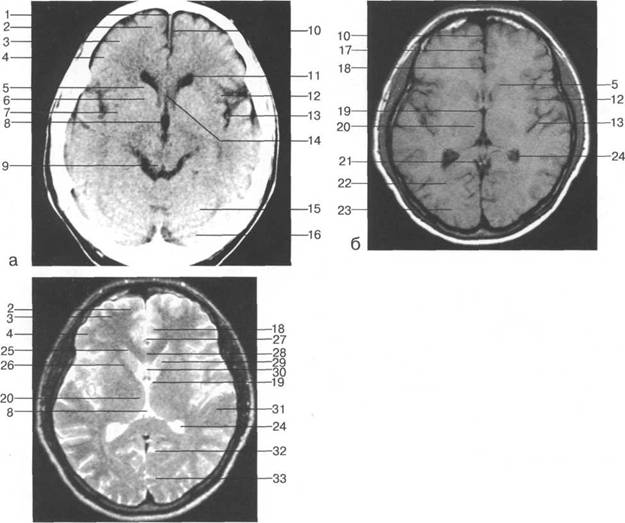

редняя мозговая артерия; 31 - межножковая цистерна.

мие; 26 - поясная борозда; 27 - головка хвостатого ядра; 28 - бледный шар; 29 - височный рог боково

цистерна четверохолмия; 14 -прямой синус; 15 -лобный рог; 16 - головка хвостатого ядра; 17 -перед

теменно-затылочная борозда; 11 - семиовальные